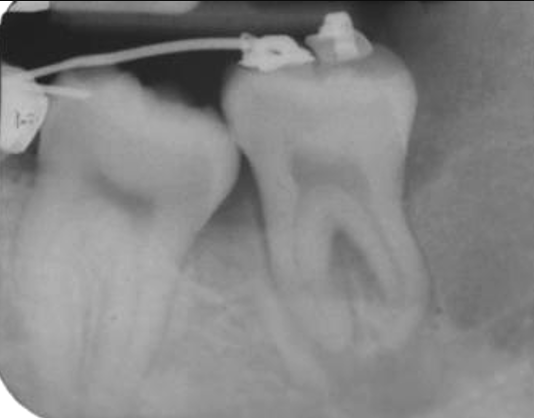

Negli anni 1997 e ’98 nel reparto di Chirurgia Speciale Odontostomatologica da me diretto all’Università degli Studi di Bologna su 262 pazienti deputati ad estrazione del dente del giudizio inferiore, abbiamo rilevato dalla ortopantomografia (OPT) 37 casi dubbi e di questi l’esame Tac, successivamente effettuato, ha dimostrato un effettivo coinvolgimento delle radici del dente con il nervo mandibolare in 31 pazienti, cioè nell’84% dei casi.

Esami radiografici quali, lastre endorali, OPT e Tac sono richiesti al fine di valutare la difficoltà ed il rischio estrattivo.